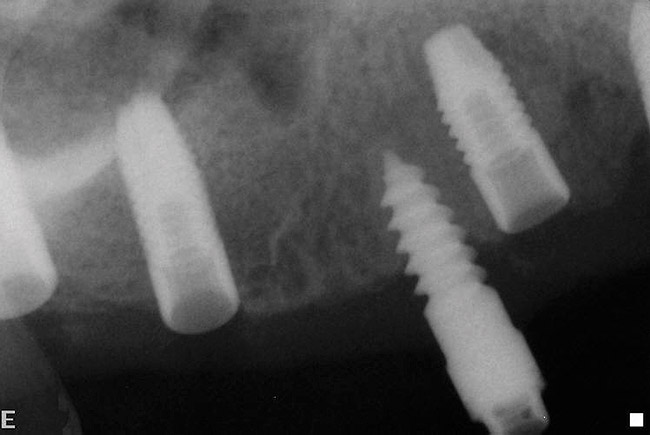

Figure 20  Post-placement periapical radiographs.

Figure 20

Figure 21  Post-placement periapical radiographs.

Figure 21

The patient was scanned with a cone beam CT scan while wearing a radiopaque scanning appliance based on her new treatment denture. Horizontal bone augmentation was confirmed radiographically, and both grafted sinuses resulted in satisfactory bone quantity for implant placement. Vertical augmentation was not attempted because of the patient’s unwillingness to forego her removable prosthesis for any period of time. Therefore, shorter implants were treatment-planned, resulting in the placement of eight implants, rather than fewer—such as six—implants, to support a full-arch fixed prosthesis. Because adequate bone and keratinized mucosa were present, a flapless, computer-guided implant insertion was performed (Figure 18). After removal of the surgical guide, placement of all eight implants could be inspected (Figure 19). Post-placement periapical radiographs are shown in Figure 20 and Figure 21.